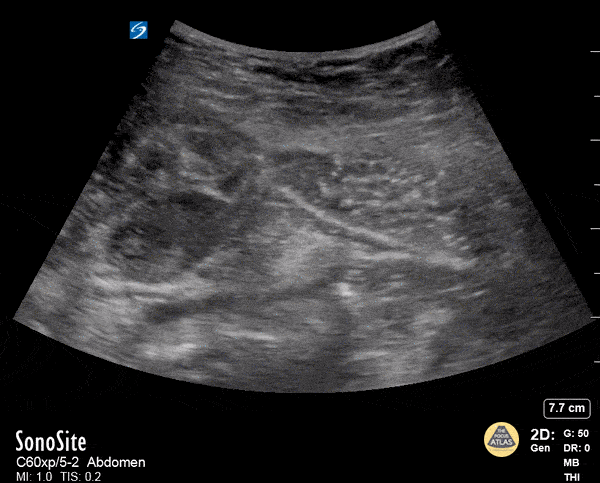

Musculoskeletal - Rectus Abdominis Hematoma

A 41 year old male presented to the ED with a painful right sided abdominal mass. On examination the area of swelling was tender to palpation and initially suspected to be a hernia. Patient had engaged in strenuous exercise the day before. Using the abdominal probe, a bedside ultrasound demonstrated a hypoechoic 4.9 x 4.7 cm hematoma within the right lower rectus muscle with active extravasation. This patient underwent successful interventional radiology embolization and had unremarkable hospital course. POCUS for abdominal masses can quickly narrow the differential for such patients, which can expedite decision making particularly in those who are hemodynamically unstable and on anti-coagulation. Max Cooper, MD Ultrasound Fellowship Director Crozer-Chester Medical Center Kevin Conor Welch, DO Ultrasound Fellow Crozer-Chester Medical Center Elena Grill, MD EM Resident Physician Crozer-Chester Medical Center